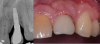

Fig 11. Pretreatment radiograph (left) of an implant placed 14 years earlier that developed peri-implant mucositis—with bone loss from the cuspid, and the initial soft-tissue perspective (right) showing puss and bleeding. Initial probing depths were 7 mm to 8 mm.

Figure 11

Fig 12. View immediately following laser assisted peri-implant mucositis treatment with an Nd-YAG laser.

Figure 12

Fig 13. At both 10 days (left) and 3 months post-treatment, resolution of the peri-mucositis is apparent in terms of bleeding and purulence.

Figure 13

Fig 14. At 3 months after laser treatment, there was absence of bleeding on probing, and shallow probing depths of only 3 mm compared to pre-treatment.

Figure 14